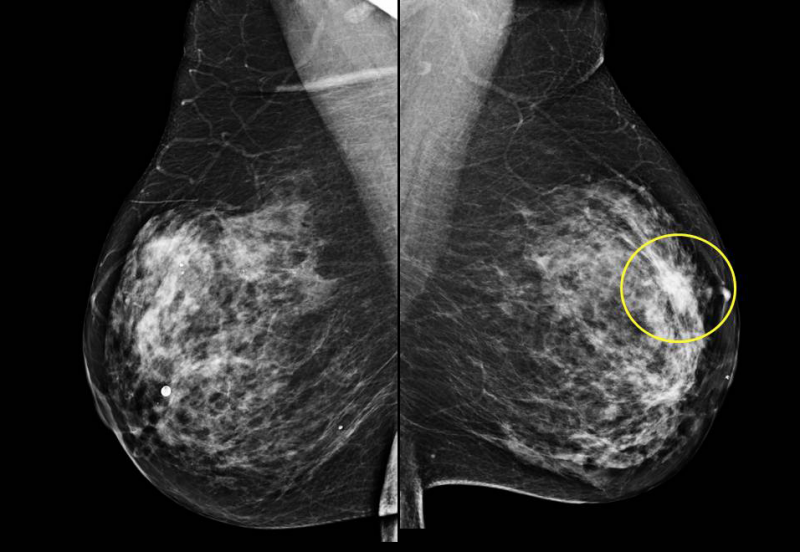

Breast cancer will affect 1 in every 8 women in their lifetime.

Breast specimen imaging equipment. Stainless steel cabinet with internal dimensions of 64 x 71 x 53 cm 25 x 28 x 21. Insight bd breast density assessment 1 benefit from instant risk stratification right at the acquisition workstation with 100 objective volumetric breast density assessment for ffdm and tomosynthesis. A method and system for producing tomosynthesis images of a breast specimen in a cabinet x ray system. By itself breast cancer is treatable and curable it only becomes a lethal killer when cancer metastasizes in the body to other organs and bones.

The result is sharp high quality images for rapid specimen verification. When a breast biopsy is performed using both stereotactic and tomosynthesis imaging guidance it is appropriate to use cpt code 19081 biopsy breast with placement of breast localization device s eg clip metallic pellet when per formed and imaging of the biopsy specimen when performed percutaneous. In the past surgeons believed that an aggressive approach to treatment was imperative for better outcomes relying on radical. Advanced 3d specimen x ray for breast surgery.

The trident system revolutionizes breast tissue imaging by incorporating a micro focused tube unique specimen image processing algorithms and amorphous selenium direct digital detector. An x ray source delivers x rays through a specimen of excised tissue and forms an image at a digital x ray detector. Specimen radiography system the most reliable pathology radiography system with the largest detector for imaging the largest gross specimens.